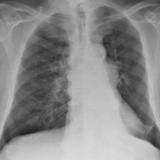

Lung Cancer

Staging

Album: Staging